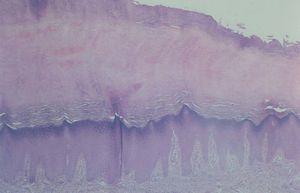

Se realizó una biopsia, que mostró una epidermis con hiperqueratosis compacta, hipergranulosis y acantosis regular moderada, a expensas de los procesos interpapilares. En la dermis se encontraron papilomatosis e infiltrados linfocitarios leves perivasculares en dermis superficial y parte de la media (fig. 2); la tinción para fibras elásticas fue normal (fig. 3). La tinción con ácido peryódico de Schiff (PAS) evidenció la presencia de elementos cocoides en la capa córnea.

Fig. 2.--Hiperqueratosis compacta, hipergranulosis y acantosis regular a moderada. (Hematoxilina-eosina x10.)

Fig. 3.--Fibras elásticas normales en dermis superficial y media. (Tinción de Gallego, x10.)